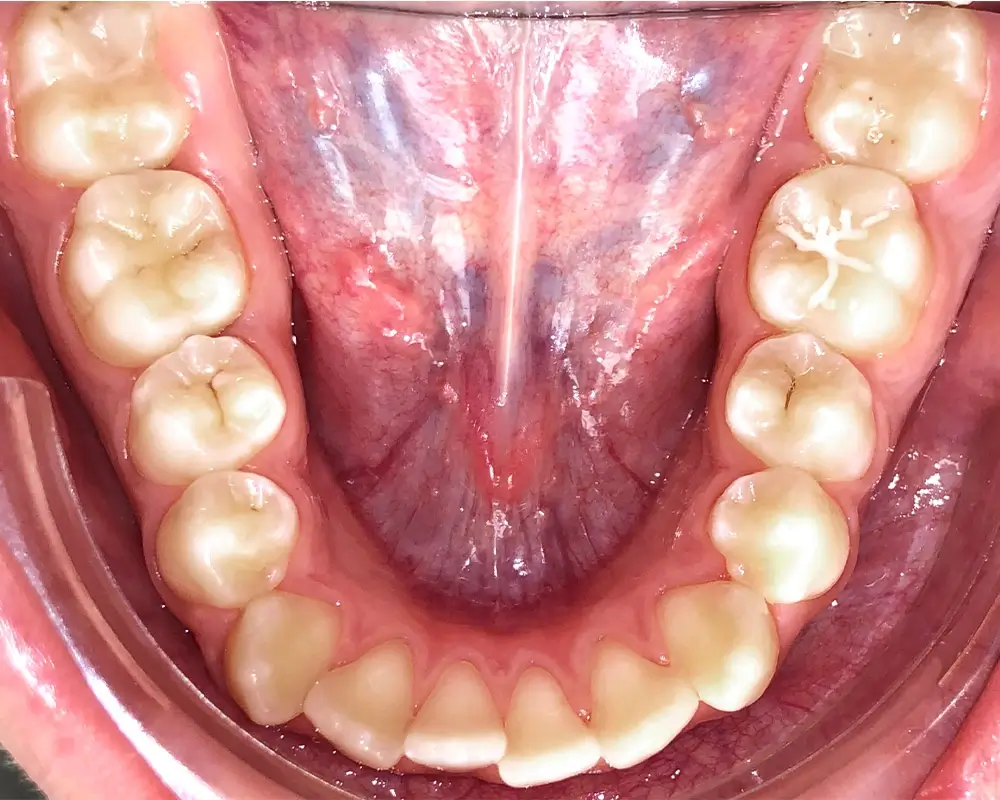

Скученность - Кейс 16

Эффективность устранения дефекта прикуса посредством элайнеров FlexiLigner.

Количество кап НЧ

20

Количество кап ВЧ

Результаты лечения